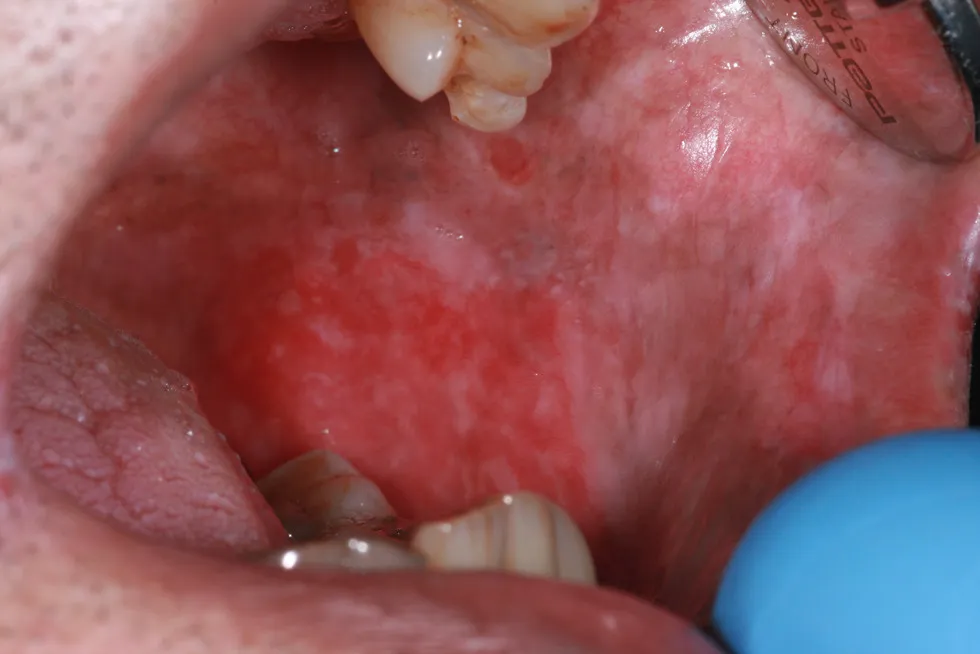

Erythroplakia

Red patches that appear on the oral mucosa, including the tongue, inner cheeks, or floor of the mouth. It is often linked to tobacco use or chronic irritation. Unlike leukoplakia, erythroplakia is more likely to be precancerous or cancerous and requires prompt evaluation.